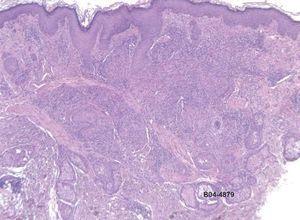

En la exploración física presentaba pápulas eritematovioláceas faciales (fig. 1), fiebre de 39 °C, con hepatoesplenomegalia, siendo el resto de los datos sin interés. En la analítica destacaba pancitopenia, transaminitis, CD4 111/mm3. La intradermorreacción a la tuberculina (PPD) fue negativa. La radiografía de tórax evidenciaba un patrón retículo-nodulillar difuso y bilateral. Los cultivos de esputo, sangre, orina y piel fueron positivos para Histoplasma capsulatum capsulatum. La biopsia cutánea de las pápulas faciales mostró una epidermis sin alteraciones, y un infiltrado inflamatorio linfohistiocitario en dermis media y profunda (fig. 2). Destacaba la presencia de unos elementos basofílicos intrahistiocitarios, reacción del ácido peryódico de Schiff (PAS) y plata metenamina positivos de 2-4 μm de diámetro con un halo periférico alrededor (fig. 3). El paciente fue tratado con anfotericina B endovenosa durante una semana, seguido de itraconazol 400 mg al día, vía oral1, observándose una mejoría clínica y analítica a los 10 días del tratamiento. El reservorio del histoplasma son las aves y los murciélagos. Sus heces contienen hongos.

Figura 2. Infiltrado inflamatorio linfo-histiocitario en dermis media y profunda (hematoxilina-eosina, x20).